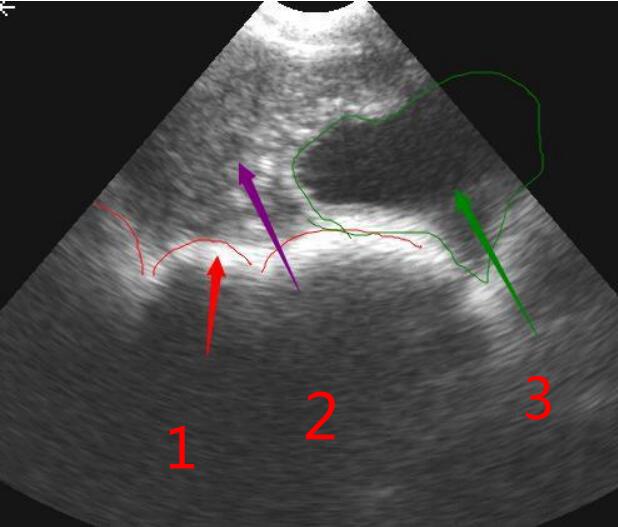

寵物b超機對犬子宮的檢查